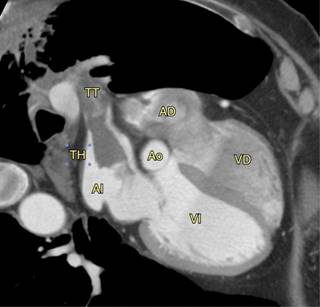

Figura 1: Angiotomografía que muestra TT = trombo tumoral en la vena pulmonar; TH = trombo hemático en la aurícula izquierda (AI); el resto de las cámaras cardiacas, aurícula derecha (AD), ventrículo derecho (VD), ventrículo izquierdo (VI) y aorta (Ao).

Individuo masculino de 67 años, campesino, con diagnóstico de adenocarcinoma pulmonar derecho con un año ocho meses de evolución. Se inició su manejo con pemetrex (500 mg/m2)/cisplatino (75 mg/m2) -de diciembre de 2015 a marzo de 2016-. Presentó síncope en marzo de 2016; se le realizó una angiotomografía, en la que se documentó progresión por trombo tumoral en la vena pulmonar superior derecha y la aurícula izquierda el 30 de marzo de 2016 (Figuras 1 a 3y video), por lo que se inició anticoagulación con apixabán en dosis de 5 mg dos veces por día desde ese día; se modificó a 2.5 mg dos veces por día hasta la fecha. En mayo de 2016 se inició su manejo con paclitaxel/carboplatino y ciclos de nivolumab en dosis de 3 mg/kg en ciclos cada 15 días. Actualmente (agosto del 2018), continúa con este último tratamiento y se encuentra en respuesta completa.